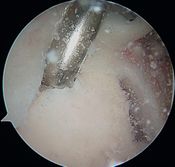

In 1985, Andrews et al. were the first to see, under arthroscopy, superior labral tears (Figure and Video) in 36 throwing athletes (sometimes associated with articular rotator cuff tears).[5]

They reported that simple debridement allowed 85% of athletes to resume their sport at the same level (Figure and Video).

Debridement of the labrum (Video) and superficial rotator cuff tears renders varying results depending on the author, ranging from 16% for Riand et al. to 85% for Andrews et al.. Labral tears can be left repaired (Figure), rotator cuff tears should not be repaired.[45][46]